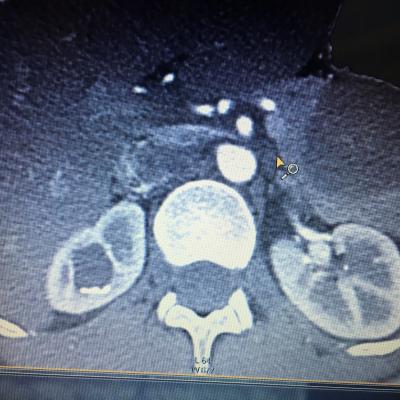

Здравствуйте,помогите, пожалуйста, с расшифровкой кт почек с контрастом. Насколько я поняла, в левой почке маленький камешек. А что за образование в правой почке? Киста с кальцинированной стенкой или камень? Спасибо за ответ!

Здравствуйте! На последнем снимке - больше данных за конкремент. Но при описании снимков должны определяться плотность образования, и нет изображения ни одного фрагмента ни одного из мочеточников. И самих снимков обычно бывает больше. Недостаточно данных для заключения.